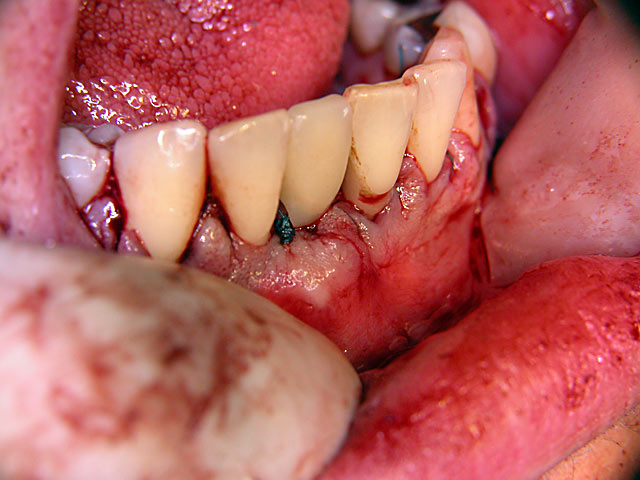

Die folgenden Patientenfälle sollen Ihnen einen Einblick in die Möglichkeiten der modernen Implantation geben.

Sofort-Implantation: